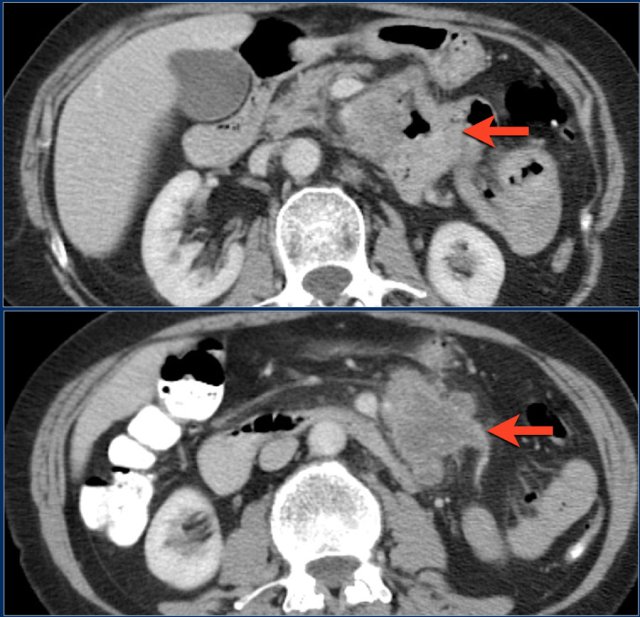

Here another adenocarcinoma located in the jejunum.

There are multiple lymph nodes (red arrow) and there is fat stranding (yellow arrows).

It should not be mistaken for mesenteric panniculitis as these large necrotic lymph nodes are pathologic.

The findings are:

- Reversed fold pattern indicating celiac disease

- Ileal-ileal intussusception (yellow arrow), in a patient with multifocal small bowel lymphoma (not all lesions shown here).

- Mesenteric lymphadenopathy (red arrows).